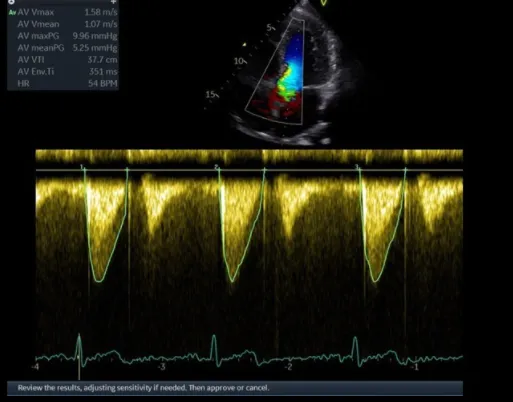

Клинические изображения

- Режимы 2D, ЦДК, PW, CW допплер

- Кардиологический автодопплер (CardiacAutodoppler)

- Режимы 2D, ЦДК, PW, CW допплер

- Кардиологический автодопплер (CardiacAutodoppler)

Кардиология

- Эхокардиография для оценки структуры и функции сердца.

- Диагностика пороков сердца, кардиомиопатий, перикардитов.

- Исследование кровотока с помощью допплерографии.

AI Auto Measure – 2D

Пакет автоматического распознавания и количественного анализа двухмерных данных в кардиологии (поддерживается 3Sc)

AI Auto Measure - Spectrum

Пакет автоматического распознавания и количественного анализа допплеровского спектра (поддерживается 3Sc)